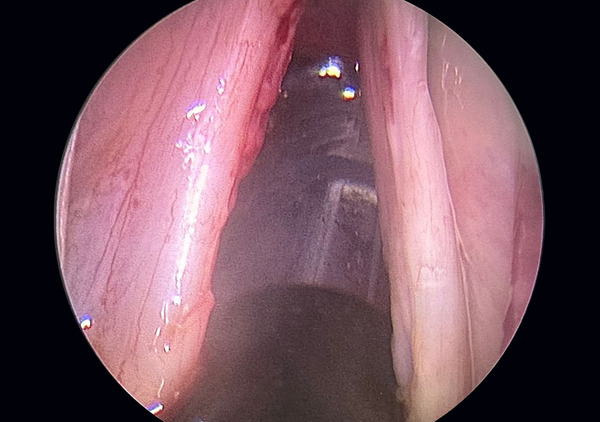

The Microflap Technique: A Closer Look

The microflap technique is performed under general anesthesia, ensuring patient comfort and safety. This is a natural orifice surgery done with a state-of-the-art 4k hd camera and monitor. Laser is used for excision and hemostasis in a few cases. Using a high-powered microscope, a small flap is created on the vocal cord. This allows for direct access to the cyst, which is then carefully removed. The microflap is repositioned, allowing the vocal cord to heal naturally.